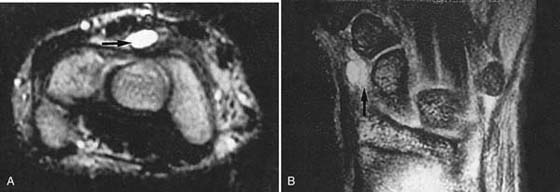

MRI is of great value in defining soft tissue abnormalities (Figs. 13-17 to 13-19, all online). In the evaluation of tumors, it cannot provide a specific diagnosis, but it can define the size of the lesion and the extent of involvement of marrow and neurovascular structures (Fig. 13-20, online).27 Other soft tissue abnormalities diagnosed more easily by MRI include ganglions, ligament tears, and cartilage abnormalities (Fig. 13-21).28,29 Dorsal wrist pain can be attributed to hypertrophy of the dorsal capsule as well as ganglions that may be occult and not palpable. Patients with dorsal wrist pain of unknown origin are therefore candidates for MRI evaluation. MRI is especially helpful in diagnosing tears of the scapholunate and lunotriquetral ligaments, particularly when dissociation of the scapholunate is not evident on plain films.30 Excellent depiction of the TFC can be achieved with MRI, but the image must be interpreted carefully; thinning of the disk occurs in many patients, but a tear of this structure is not diagnosed unless an avulsion from the ulnar or radial insertion can be observed.31-33

Figure 13-21 Ganglion. A, This axial magnetic resonance image demonstrates a dorsal mass (arrow) that was not palpable on clinical examination. B, Coronal magnetic resonance image in another patient showing a mass in the abductor canal (arrow).

MRI plays a limited role in the examination of patients with possible carpal tunnel disease. By and large, the diagnosis of this problem should be reached clinically, but MRI may be used occasionally if the symptoms derive from a soft tissue mass or an infection within the carpal tunnel.59,60 Indications for wrist MRI include atypical symptoms, a lack of EMG findings, high clinical suspicion for a mass, young patient age (possible congenital anomalies), and recurrent symptoms in postoperative patients.

On MRI, the flexor retinaculum is normally taut to minimally convex, the median nerve is of uniform size (4 × 2 mm) and ovoid in shape with signal isointense to muscle, and the flexor tendons are not distinguishable from one another on T2-weighted sequences. MRI findings of CTS include volar bowing of the flexor retinaculum, synovitis of the tendon sheaths within the carpal tunnel, focal enlargement of the median nerve at the level of the pisiform, and increased signal of the nerve itself. The median nerve may alternatively appear flattened. Note that these findings are nonspecific in the absence of symptoms. High signal within the median nerve is the least reliable sign and is often seen in asymptomatic individuals. Mild bowing of the flexor retinaculum may be physiologic; thus, CTS should not be suggested unless this finding is marked. Masses rarely cause CTS, but the search for masses must be diligent. Ganglion cysts, lipomas extending from the thenar or hypothenar eminences, or focal amyloid deposition may be causative lesions. A dedicated extremity MRI may be a cost-effective way to make this diagnosis.

Ulnar Nerve Compression (Guyon’s Canal)

Compression of the ulnar nerve also may occur at the wrist, resulting in tingling and pain along the hypothenar region and ulnar side of the fourth and fifth fingers. The ulnar nerve, along with the ulnar artery and vein, travels within Guyon’s canal. This space lies superficial to the retinaculum of the carpal tunnel, adjacent to the hook of the hamate. Processes that affect or extend into this space may cause the characteristic symptoms.

Guyon’s canal is formed on the medial side by the pisiform and flexor carpi ulnaris muscle and on the lateral side by the hook of the hamate. The splitting of the flexor retinaculum forms the roof of Guyon’s canal. Within the canal lies the ulnar nerve, ulnar artery, and vena comitans.61 Pain in the ulnar aspect of the palm may be caused by a pathologic condition in the canal and may involve the hook of the hamate, pisiform, ulnar artery or vein, or ulnar nerve. A tumor such as a lipoma or ganglion that extends into or arises within the canal also may cause symptoms by compressing any of these structures.

Fractures involving the hamate or pisiform may be difficult to visualize on plain films and are best evaluated on a carpal tunnel view or CT scan. An anteroposterior oblique view also should be obtained to assess the possibility of pisotriquetral arthritis. Pisotriquetral arthritis may be idiopathic or the result of a fracture. MRI is the best option for examining vascular and other soft tissue structures. Routine MRI and MRA can definitively establish vessel patency noninvasively.

As with CTS, MRI may reveal masses, most commonly ganglion cysts or inflammatory changes within Guyon’s canal. Compression of the ulnar nerve most commonly results from fibrous bands, which may not be visualized on MRI. Beware of looped ulnar vessels, which may mimic ganglia in this region.